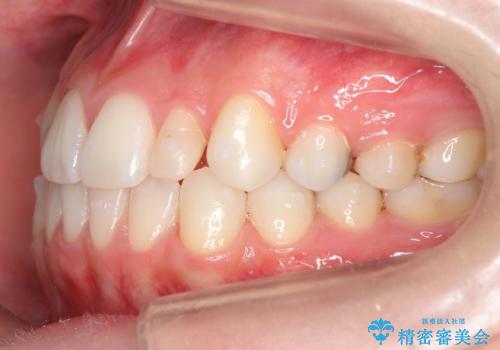

- 前歯のがたつきと小さな歯の形を治したいと来院。

前から2番目の歯が小さく、細くとがった形になっていました。

大きくしようにも、幅が少ない上に、また、内側に入ってしまっているため、矯正治療で前歯を並べてからセラミックでかぶせることにしました。

いきなりセラミックでかぶせるよりも手間をかけた分、自然な仕上がりになっています。

先に矯正治療をすることで、下の前歯を内側に入れることができ、上の歯のセラミックの幅や厚みを取ることができました。